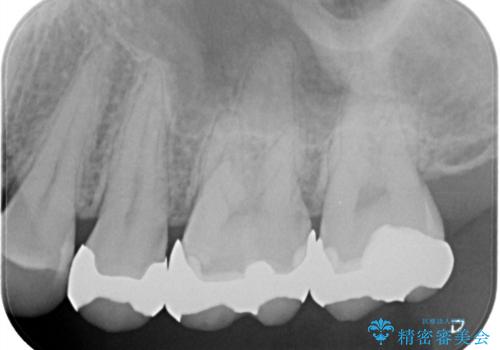

- 銀歯の入っている部分にフロスが引っかかるため、銀歯を適合の良い白いセラミックインレーにやりかえることを提案させていただきました。

一番奥の歯は銀歯に覆われている範囲が多いため、強度などを踏まえ被せ物にしました。

その他2本は詰め物です。